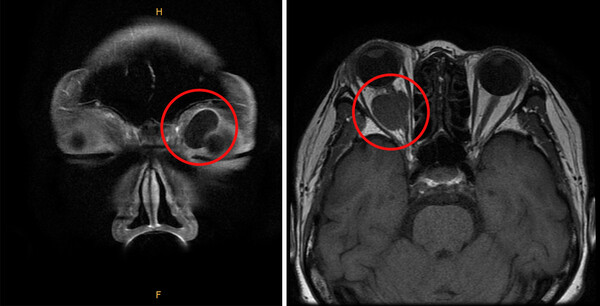

안와종양 진단 방법은 환자의 얼굴을 관찰하고, 만져지는 덩어리가 있는지 확인하며, 덩어리에서 소리가 들리는지 확인한다. 이후 안구돌출계를 이용해 눈에 안구 돌출이 발생했는지 확인한다. 또한 명백한 이상이 관찰되면 이후 CT, MRI 등 영상검사를 시행한다.

안와 양성종양은 일반적으로 수술을 통해 제거할 수 있으나, 발생 위치에 따라 합병증 발생 위험이 있을 수 있으므로 신중하게 치료 방향을 결정해야 한다. 먼저 수술 전 CT 및 MRI 검사를 통해 종양의 크기, 위치, 성상을 정확하게 파악하고 분석한다.